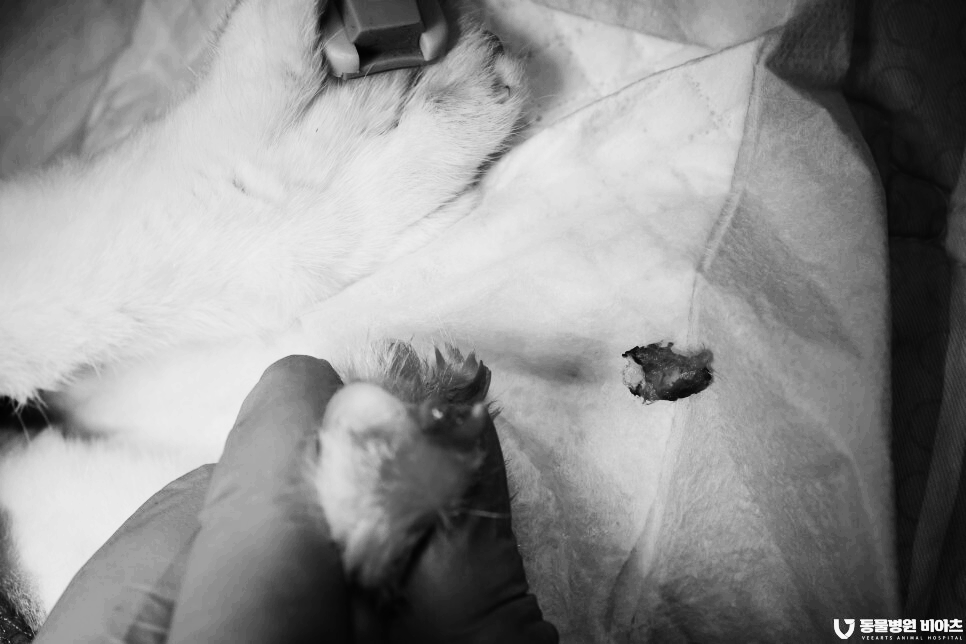

치료 (호흡 마취, 부분 골절된 발톱/ 육아종 제거)

골절된 발톱 부위에

염증이 많습니다.

염증이 생겨서 벌어진 틈으로 육아종이 증식하였습니다.

또한 출혈도 발생하고 있습니다.

제거된 병변입니다.